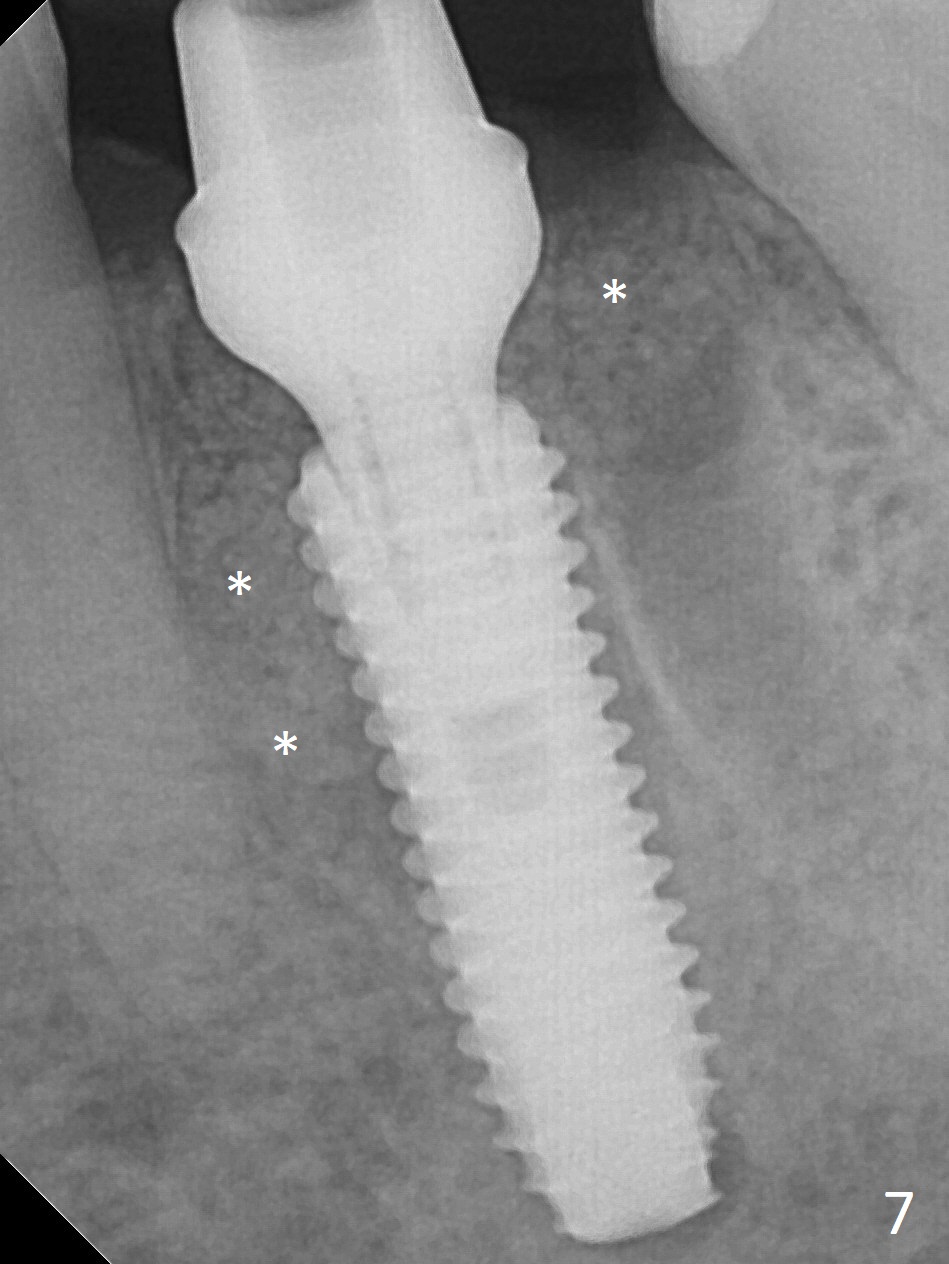

When the patient returns 9 months later, there is severe buccal gingival recession and abscess at #19 (Fig.1 *) with large mesial periradicular radiolucency (Fig.2 *). The septum is thin and the buccal crest is low after extraction (Fig.3 * (mesial root vertical fracture)). Osteotomy is initiated in the mesial socket immediately against the septum (Fig.4.5) with ~ 5 mm in the native bone. Due to severe buccal plate resorption, a shorter implant is placed (Fig.6; 5x15 mm in stead of 18 mm). There is at least 2 mm gap buccally for Vanilla Graft, which is also placed next to the implant and the neighboring root (Fig.7 *). There is clearance from the Inferior Alveolar Canal (Fig.8 red dashed line). Both the mesial and distal sockets heal 5.5 months postop (Fig.9), although the apical portion of the distal socket was not filled with allograft (Fig.7). The implant was placed mesial. The straight abutment (6.5x4(4) mm) (Fig.10) is changed to an angled one (5.5 x15 degrees 3 mm cuff (Fig.11)) before impression. The implant is also placed buccally. Therefore the implant position is far more important than its length. The abutment is retightened 2.5 months post cementation, which is related to mesiobuccal placement of the implant (Fig.12). An ideal trajectory is determined by drawing 2 horizontal lines (at crestal and apical levels: red lines in Fig.13), finding a central point of each line (vertical short line) and joining these 2 central points (Fig.14 pink line). In fact the ideal osteotomy should have been established distal to the septum in this case. Guided surgery may alleviate the issue. The crown is not loose, but the patient feels that the implant tooth cannot sustain mastication. In fact the screw is removed with hand driver (not wrench). The abutment hex is rounded and worn. A new 5.5x4(4) mm abutment is placed (without knowledge of previous use of an angled abutment) with mesial reduction to reduce undercut and buccodistal margin lowered to reduce gingival embrasure. It is that the straight abutment could decrease the chance of screw loosening. Otherwise the implant has to be removed for better trajectory.